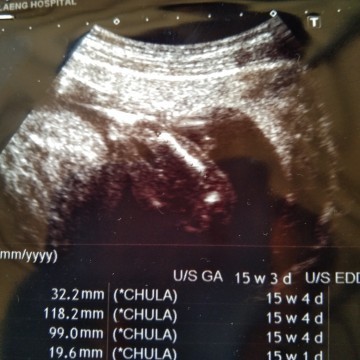

ซาวหน้าท้อง

คือหมอซาวแต่ไม่ให้ดูอะไรเลยแล้วก้อไม่ อทิบายด้วยอยากทราบว่าในภาพไหนหัวไหนตัวไหนแขนไหนขาคะ

ในรูปน่าจะขาค่ะแม่